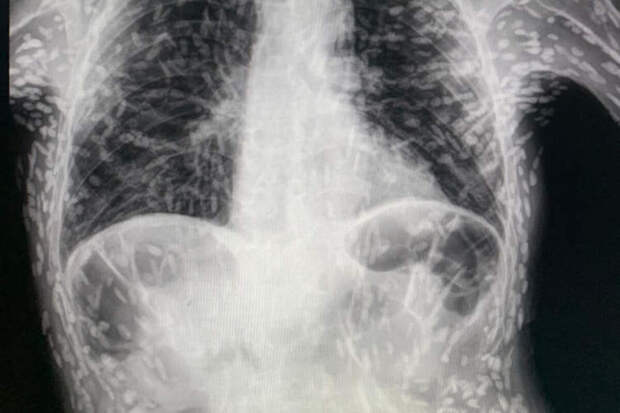

Врач из Бразилии опубликовал в соцсетях рентгеновский снимок мужчины, болеющего цистицеркозом, пишет Oddity Central. На кадре видно, что практически все тело мужчины заполнено яйцами ленточного червя.

Доктор Витор Борин де Соуза опубликовал рентгеновский снимок пациента, чтобы показать своим подписчикам, насколько опасна инфекция ленточного червя.

Врач добавил, что белые пятна, которые можно увидеть на фото, - яйца паразита. К счастью, мужчине, пришедшему на осмотр из-за непрекращающегося кашля, яйца не представляли опасности, так как все они были кальцифицированы [нежизнеспособны]."Если это не вызывает никакого дискомфорта, жизнь продолжается", - добавил медик.

Исследования показали, что массивный цистицеркоз, как случай, показанный на рентгеновском снимке, возникает у пациентов с ослабленным иммунитетом, которые имеют более уязвимую иммунную систему.